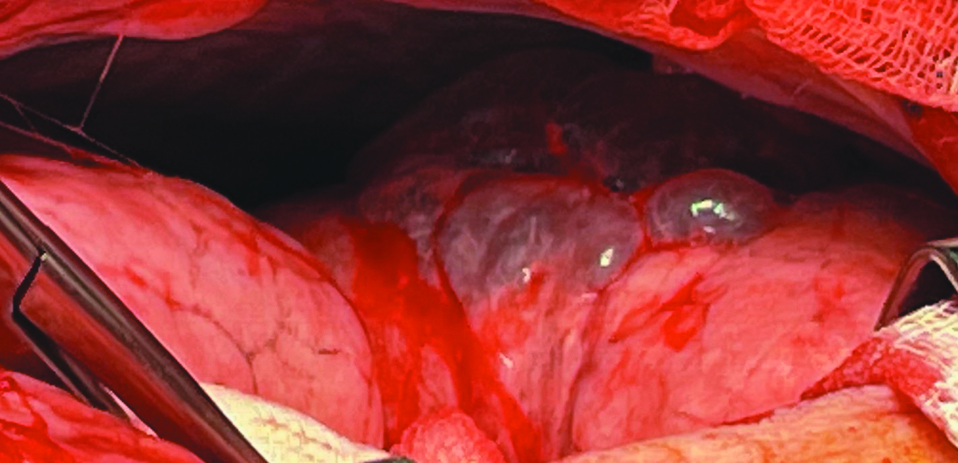

Process of the surgery. After the longitudinal sternotomy, a large size pulmonary hernia of the right lung was visualized (Fig. 2).

Figure 2. Mediastinal pulmonary hernia of the anterior mediastinum of the right lung.